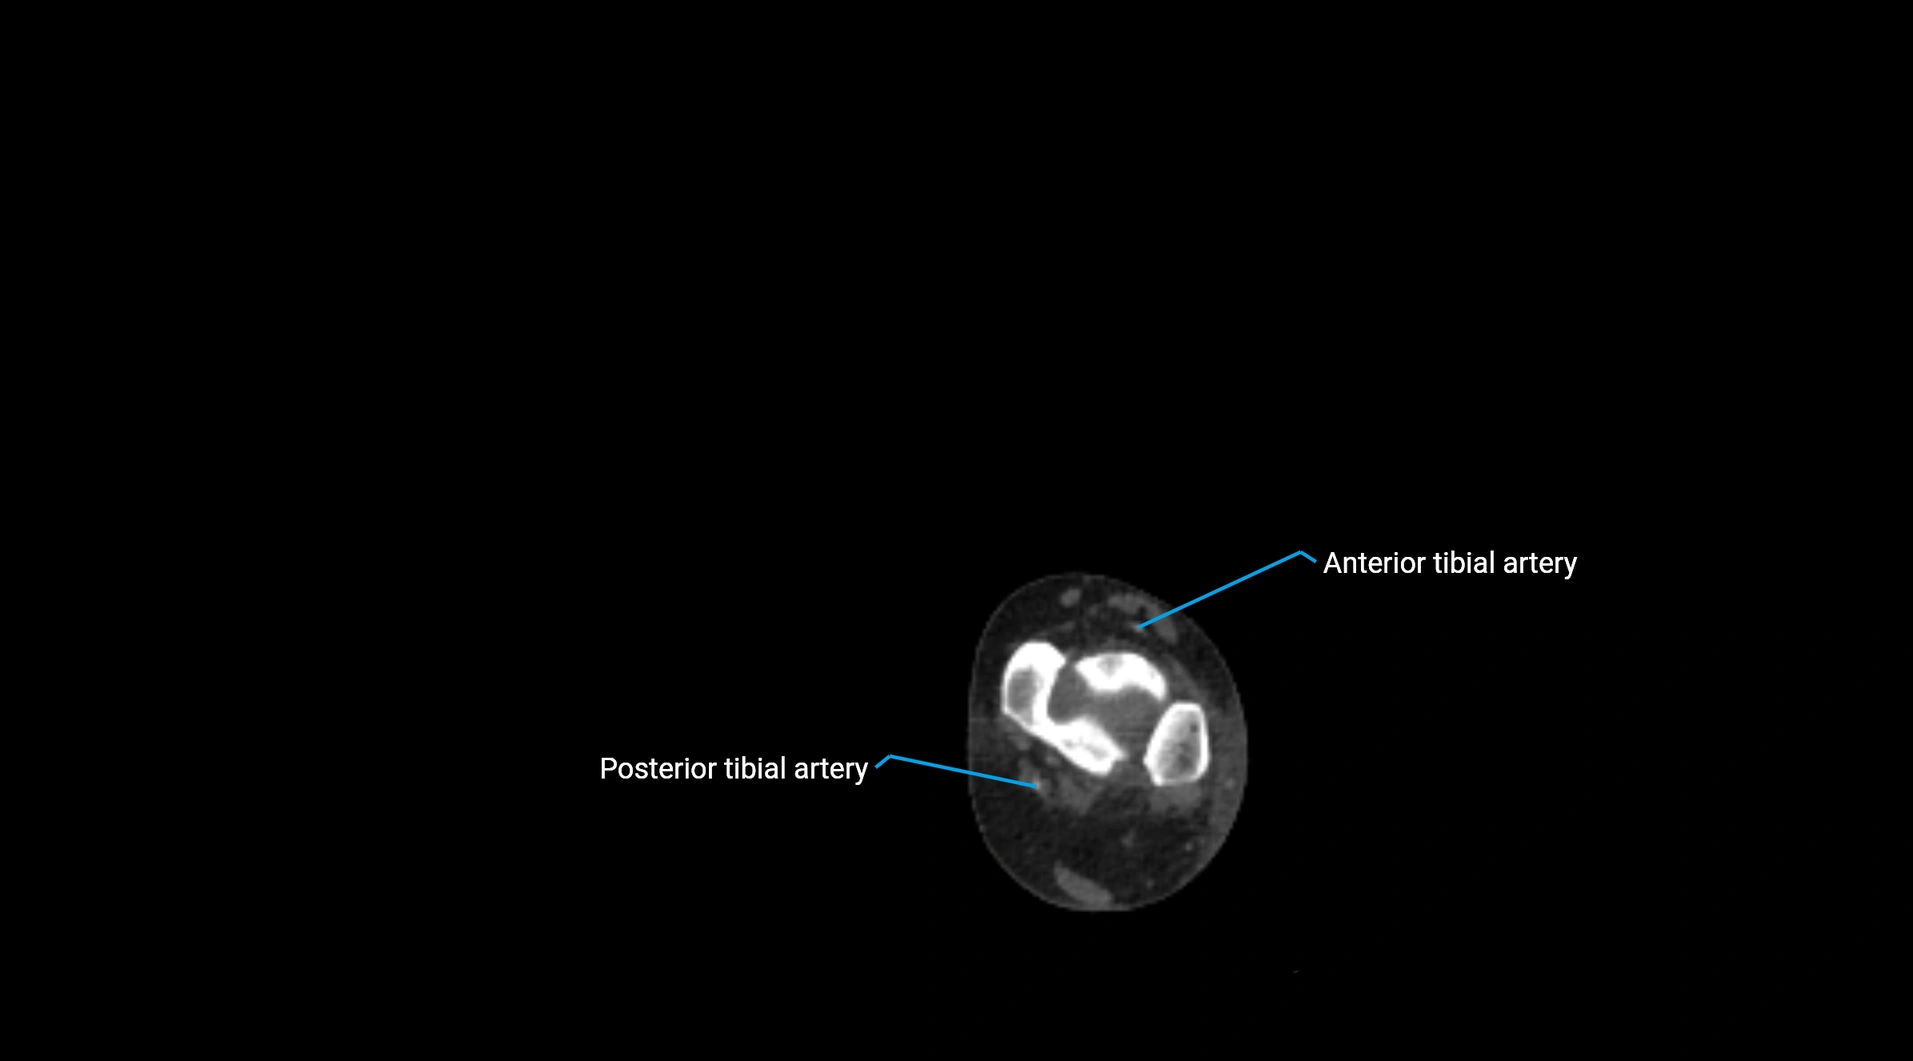

CT images

image

CT Appearance

Non-contrast CT:

• Appears as a tubular soft tissue structure anterior to vertebral bodies

• Calcified atherosclerotic plaques appear as hyperdense foci along the wall

• Useful for screening abdominal aortic aneurysm (AAA) size and mural calcification

Contrast-enhanced CT (CTA):

• Gold standard for abdominal aortic imaging

• Provides excellent detail of lumen, wall, aneurysm, thrombus, and branch vessels

• Multiplanar and 3D reconstructions help in aneurysm measurement, stent graft planning, and dissection evaluation

• Detects acute rupture, traumatic injury, or occlusion with high sensitivity